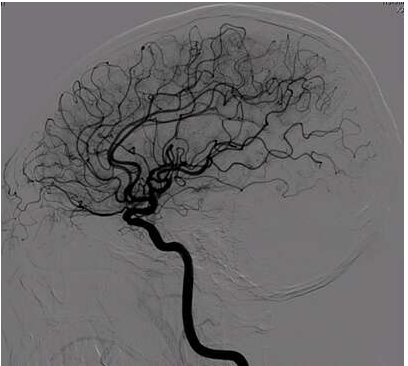

血管造影,是一种介入检测方法,将显影剂通过导管注入血管里。因为X光无法穿透显影剂,血管造影正是利用这一特性,通过显影剂在X光下所显示的影像来诊断血管病变的,比如下面就是一张脑血管的影像图。